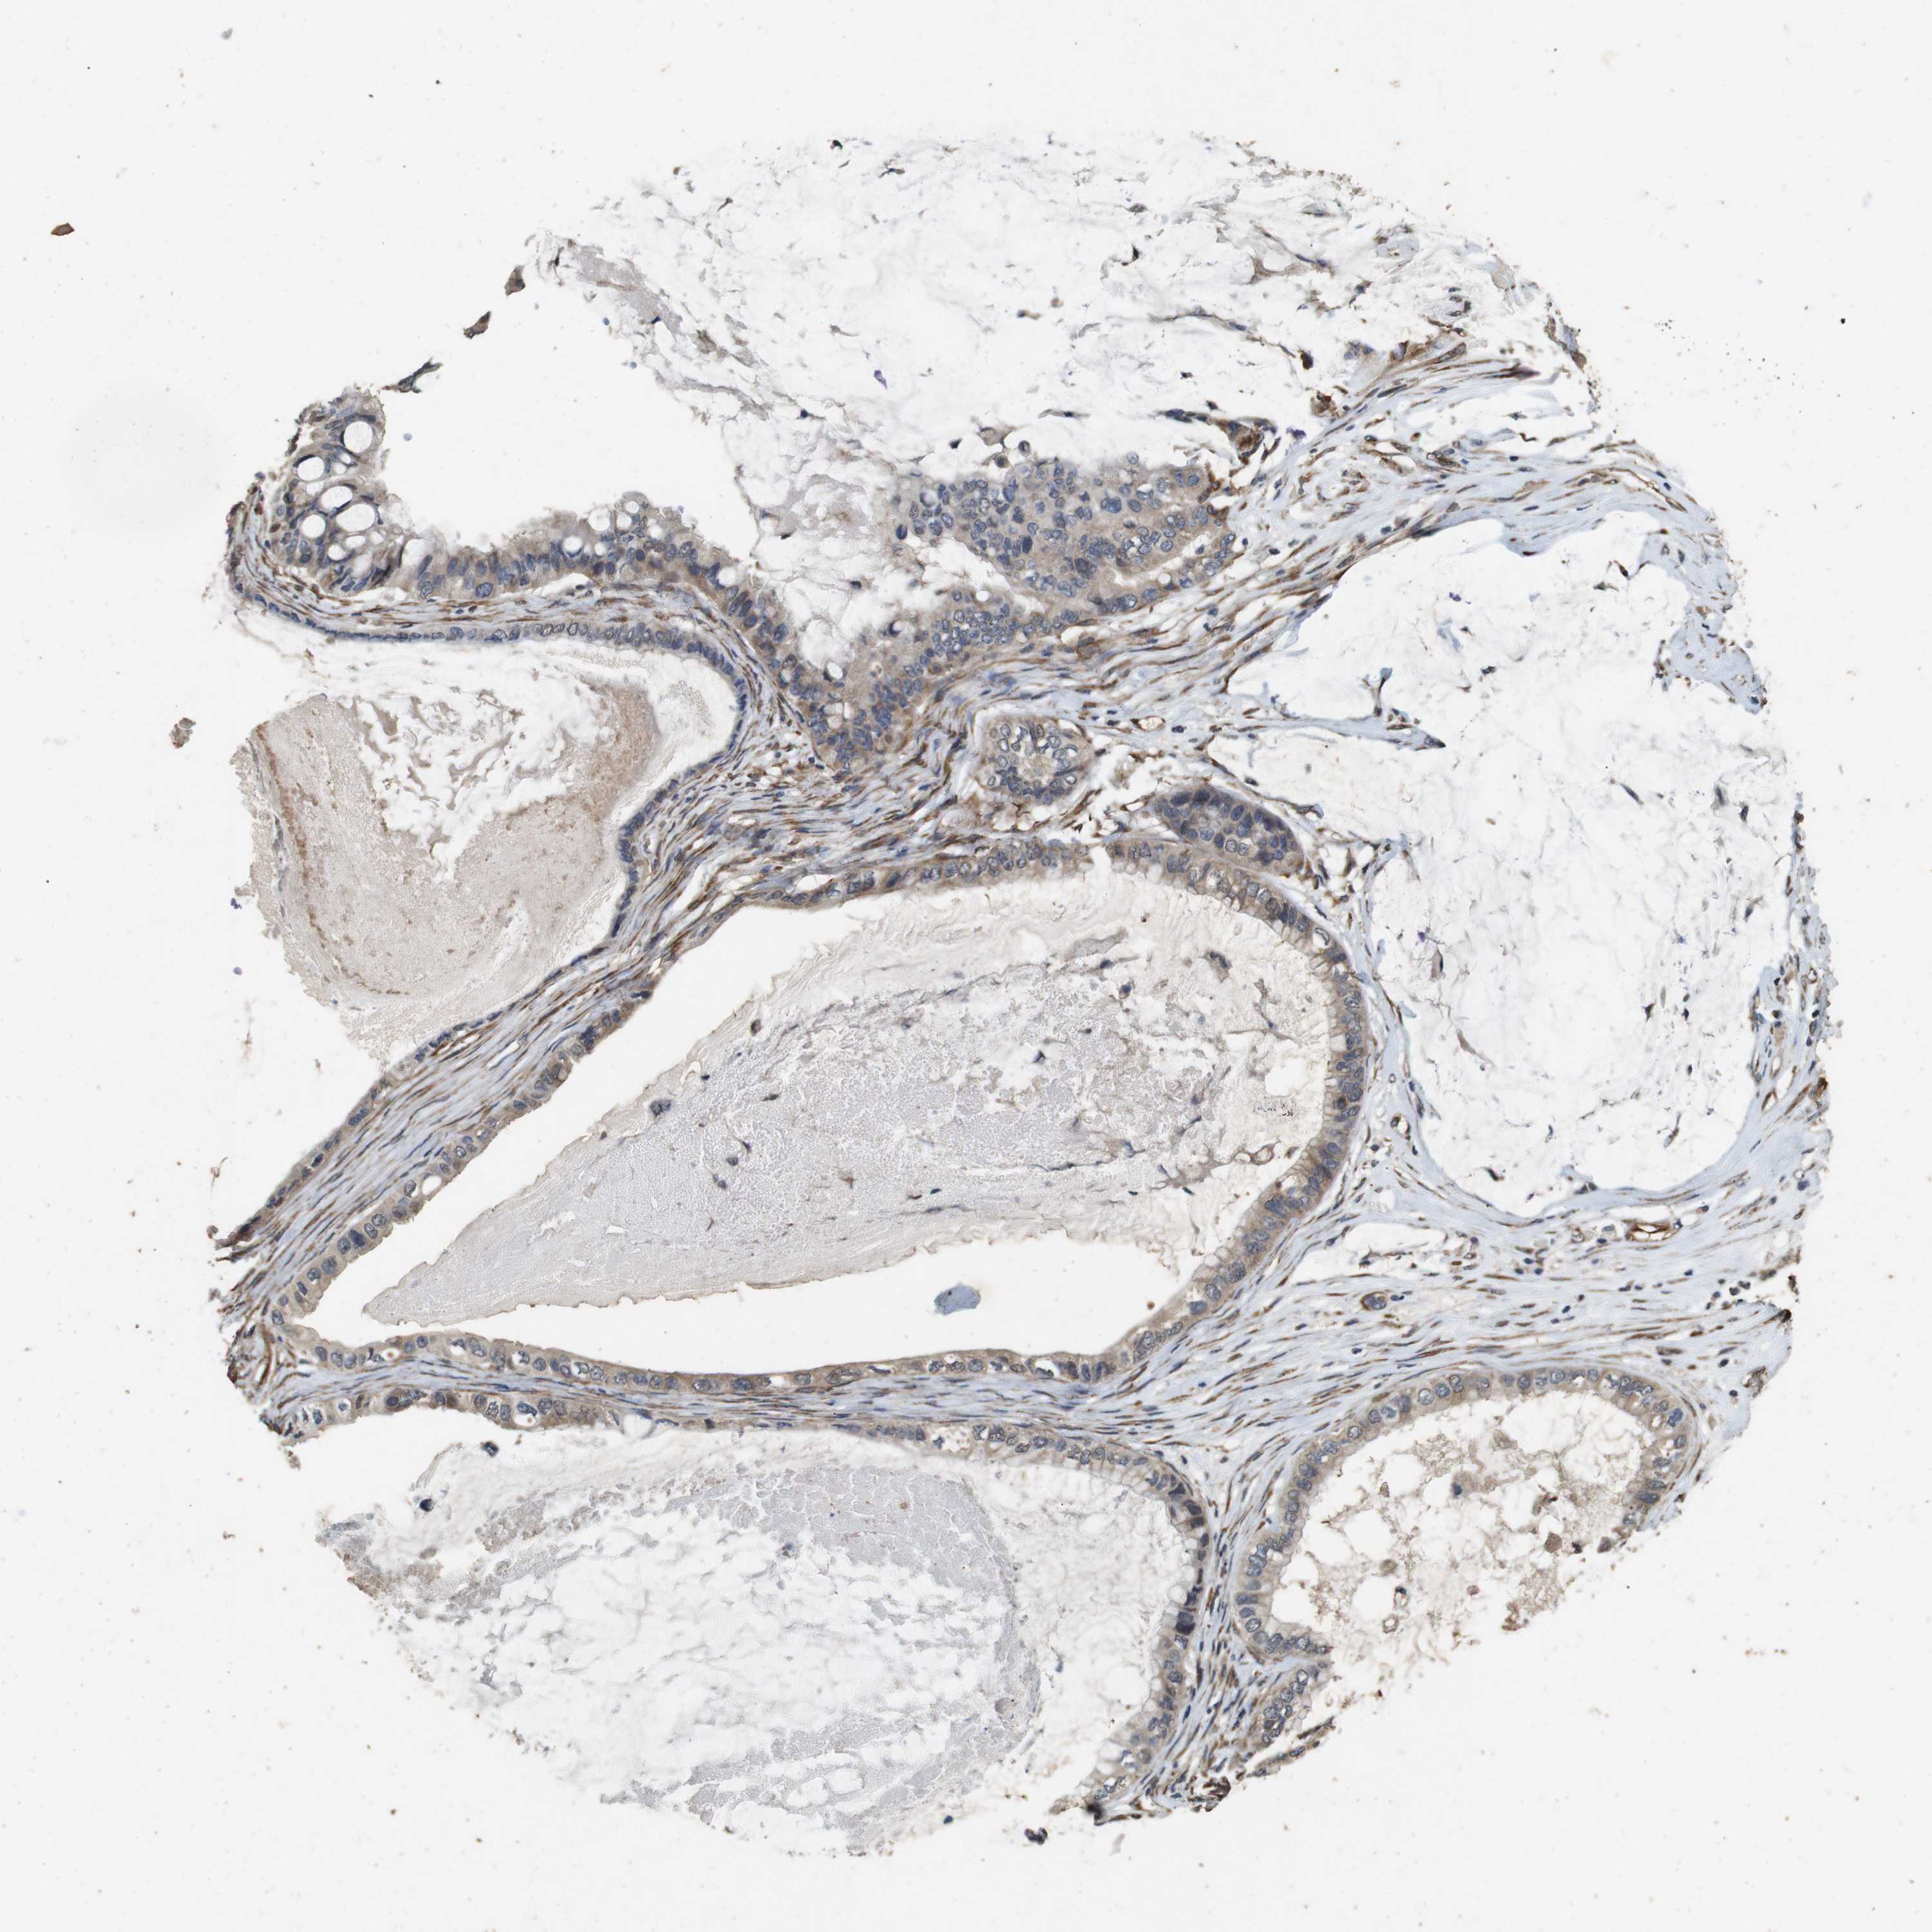

OVARIAN CANCER - Protein expressioni

A mouse-over function shows sample information and annotation data. Click on an image to view it in a full screen mode. Samples can be filtered based on level of antibody staining by selecting one or several of the following categories: high, medium, low and not detected. The assay and annotation is described here.

Note that samples used for immunohistochemistry by the Human Protein Atlas do not correspond to samples in the TCGA dataset.

Antibody stainingi

Antibody staining in the annotated cell types in the current human tissue is reported as not detected, low, medium, or high, based on conventional immunohistochemistry profiling in selected tissues. This score is based on the combination of the staining intensity and fraction of stained cells.

Each image is clickable and will lead to virtual microscopy that enables deeper exploration of all samples and also displays staining intensity scores, fraction scores and subcellular localization as well as patient and tissue information for each sample.

Antibody HPA014166

Antibody HPA025240

Cystadenocarcinoma, serous, NOS

Carcinoma, endometroid

Cystadenocarcinoma, mucinous, NOS

Carcinoma, NOS